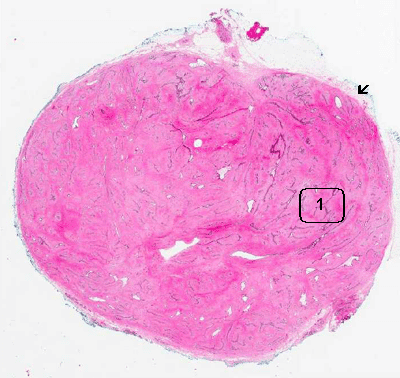

• The mass is about 1.4 cm across in greatest dimension. It is almost round and with a very well demarcated margin. The tumor can be well excised from the surrounding tissue with a clear plane (arrow). Only small amount of adipose tissue are rimming the nodule. A clean separation plane is one of the characteristic features of benign tumors. In contract, invasive carcinomas infiltrate into the surrounding tissue and will not produce a clean surgical plane for separation.

• Fibroadenoma is a biphasic tumor which has a mesenchymal component and epithelial component. Both of them are benign in nature. The tumor cells lacks features of malignant tumors that include high nucleus to cytoplasm ratio, hyperchromatic nuclei, enlarged and irregular nuclei, pleomorphism, prominent nucleolimitotic figures, necrosis, iand nfiltrative growth pattern.